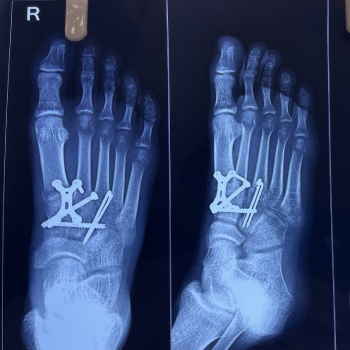

Lisfranc Injury Treatment

Lisfranc injury treatment includes immobilization, rest, pain management, and physiotherapy. Moderate to severe cases may require surgical fixation, followed by structured rehabilitation programs to restore stability, improve mobility, and ensure proper long term recovery.